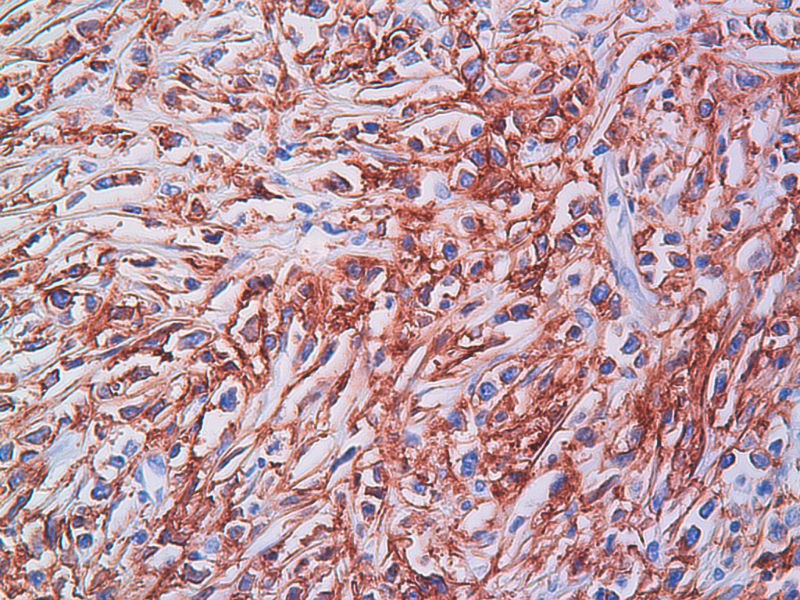

免疫组化染色:CA125(-),PLAP(-),NSE灶状阳性,Vimentin(+),a-inhibin(-),CK7(-),CK20(-),CD15(-),PSA(-),S100(-),MyoD1(-),CD38(-),CD56(-),HMB45(-),CK8(-),NF(-),CGA(-),syn(+),MPO散在(+)可能是炎细胞吧,LCA(+),CD133(+).

今天又做了免疫组化,请大家帮看看。CD10(-),CD138(-),CDX2(-),CD3(-),CyclinD1(-),CD2(-),CD117(-),CD7(-),CD30(-),CD23(-);CD20强(+),BCL-2,Bcl-6,EMA,PAX-5,MUM-1,CD5,ALK,CD68都是散在阳性,大家帮确定一下是否阳性。B细胞淋巴瘤可以确定了,不知是哪种类型的?

是的,syn(+),LCA(+), CD79a阳性, CD3阴性,NSE是局部胞核,胞浆着色,主要是胞浆着色;SYN也是局部,主要是胞核着色,胞浆很少。不对吗?我也迷糊。也许我看错了,不像那种典型的胞浆颗粒状着色。大家帮看一看。